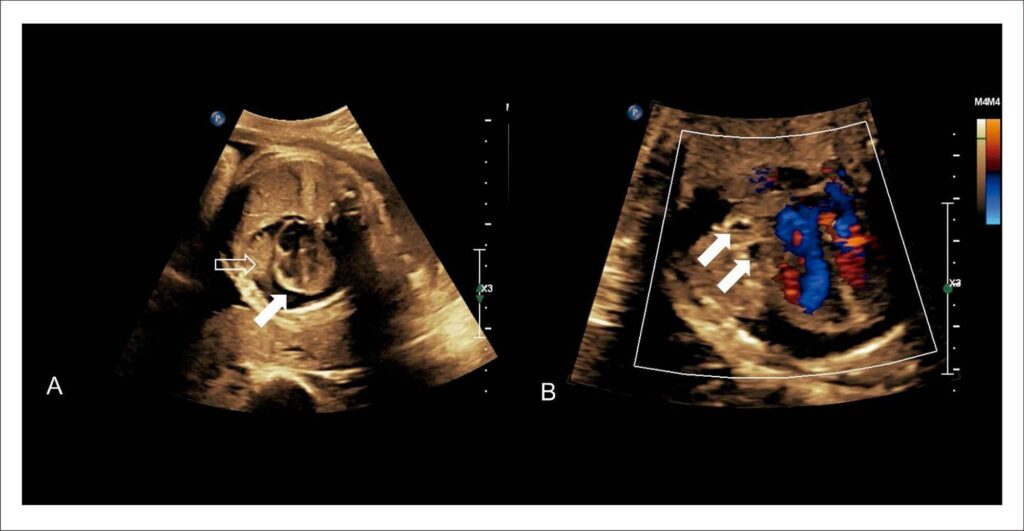

Os teratomas, embora usualmente benignos, podem ter origem embrionária em uma ou mais das 3 lâminas germinativas, o que determina histologia complexa, com a possibilidade de áreas simultâneas de tecido maduro e imaturo. Os teratomas intrapericárdicos são tumores de baixa incidência, mas que frequentemente invadem mediastino e comprimem estruturas adjacentes, levando ao óbito. Apresentamos um caso de teratoma intrapericárdico diagnosticado em um feto de 22 semanas de gestação.